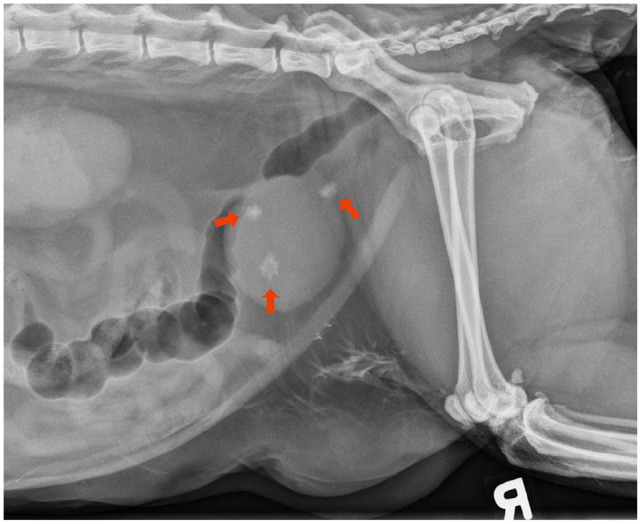

Case summary: A 10-year-old female neutered domestic shorthair cat presented with stranguria. The cat was bradycardic and had a firm urinary bladder on physical examination. On initial laboratory testing, the cat had severe azotemia with a creatinine of 15.8 mg/dl (reference interval [RI] 1.1-2.2), blood urea nitrogen of 217 mg/dl (RI 18-33) and potassium of 8.9 mmol/l (RI 3.5-5.0). Abdominal radiography revealed three cystoliths, with one cystolith suspected of being lodged within the trigone. Ultrasound of the abdomen showed marked suspended echogenic debris within the urinary bladder. Corynebacterium urealyticum was isolated from aerobic bacterial urine culture. A cystotomy was performed, and crystallographic analysis of the removed cystoliths showed they were composed of 94% struvite and 6% calcium phosphate. The cat recovered well and was discharged 2 days postoperatively. Three weeks postoperatively, the cat showed resolution of all clinical signs and azotemia.